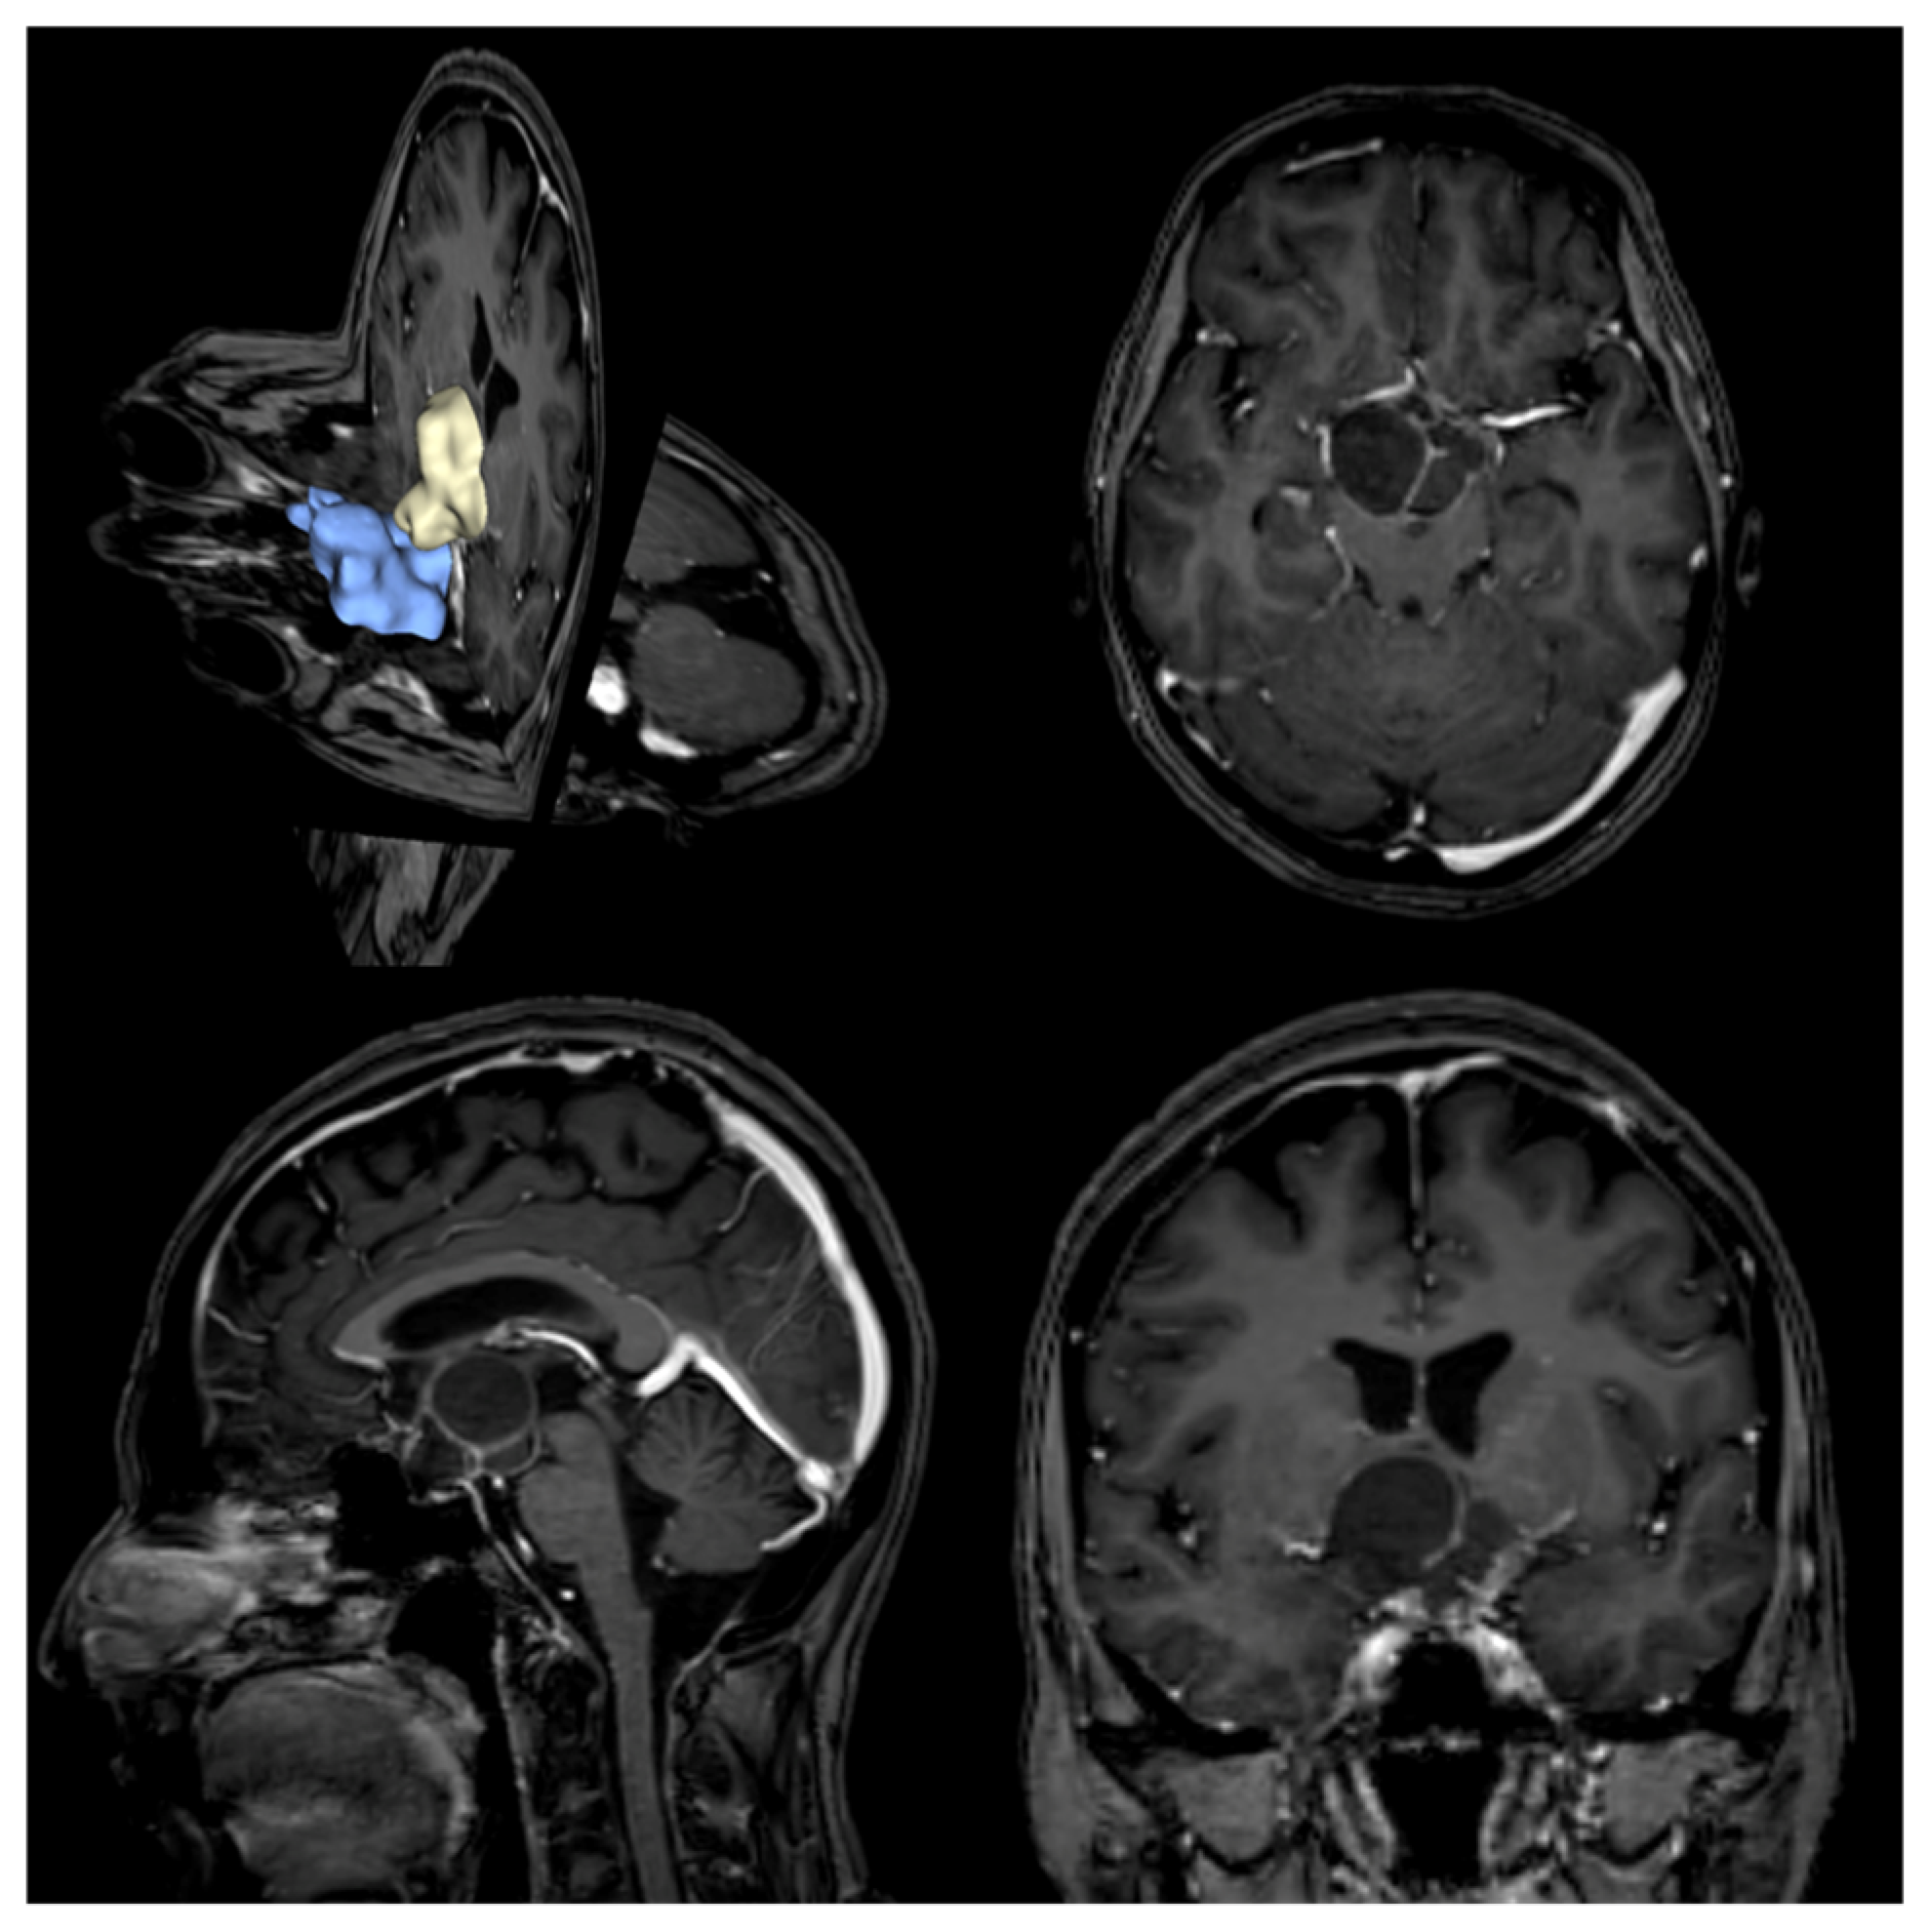

2.2.2. Imaging Study

- MRI imaging: Using a 3-Tesla Philips Achieva scanner (Philips Healthcare, Best, The Netherlands), 3D T1w (before and after gadolinium injection), FLAIR and T2w images were acquired.

- CT imaging: Acquired using a General Electric OPTIMA 660 scanner (GE Healthcare, Chicago, IL, USA), including a volumetric acquisition with bone window reconstruction.

2.3.1. Volumetric Analysis